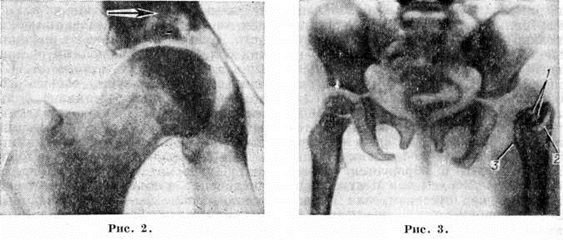

В зависимости от этого Коксит делятся на острые и хронические. Наиболее ранние клинические, проявления Коксит— боль в области поражённого сустава или в других сегментах конечности, ограничение подвижности в суставе и образование миогенных контрактур (смотри полный свод знаний) с установкой конечности в порочном положении. Выпот в полости тазобедренного сустава приводит к образованию припухлости над ним, которая определяется лишь при значительном скоплении жидкости или слабом развитии мышц — у детей или истощённых субъектов. В ряде случаев экссудат выходит за пределы суставной капсулы, и образуется абсцесс (смотри полный свод знаний) или флегмона (смотри полный свод знаний). Местная температура над суставом, как правило, повышена; степень повышения её является показателем остроты воспалительного процесса. Общие симптомы (лихорадка, слабость, вегетативные нарушения и другие), как и местные, могут быть выражены в различной степени; это определяется характером возбудителя инфекции, реактивностью организма, его исходным состоянием и так далее. При гнойных и туберкулёзных Коксит в дальнейшем происходит разрушение вертлужной впадины, головки и шейки бедренной кости с вывихом и смещением последней кверху, укорочением конечности и усилением её порочного положения. Особенно большая деструкция наблюдается в детском возрасте, что приводит к замедлению роста конечности, а также, в связи с её порочным положением, к лордотическому и сколиотическому искривлению поясничного отдела позвоночника (смотри полный свод знаний Лордоз, Сколиоз) и вторичной деформации таза. Последствием гнойных Коксит нередко является костный анкилоз (смотри полный свод знаний) сустава. Для туберкулёзного Коксит более характерен фиброзный анкилоз. В случаях ограничения воспаления синовиальной оболочки в покровном хряще и костных элементах сустава развиваются дистрофические изменения, приводящие к более или менее выраженному артрозу с соответствующим нарушением функции сустава. Вторичные деформации и явления артроза появляются также в других суставах конечности в связи с изменением нагрузки на них. Осложнения при Коксит определяются его этиологией, общим состоянием организма больного, своевременностью и правильностью лечения. Наиболее характерно образование абсцессов и свищей при туберкулёзных и гнойных Коксит, что в дальнейшем может привести к развитию амилоидоза внутренних органов (смотри полный свод знаний Амилоидоз). Грубые разрушения элементов сустава приводят к патологический установке конечности и деформации других частей скелета. Неблагоприятным последствием синовиальных форм Коксит следует считать анкилоз тазобедренного сустава в порочном положении. ДиагнозДиагностика Коксит основана на клинический, рентгенологическое и лабораторный исследовании больного. При осмотре изучают внешний вид больного и поражённый сустав. В зависимости от этиологии Коксит, длительности болезни, общего исходного состояния организма больного его внешний вид может характеризоваться как незначительными, так и выраженными изменениями, вплоть до крайних степеней истощения. При осмотре сустава выявляют увеличение его объёма, изменение цвета кожи над ним, усиленный рисунок подкожной венозной сети, отдельные выбухания, обусловленные скоплением экссудата, свищи с различным количеством гнойного отделяемого. Имеет значение характер гноя, его количество, цвет и запах. Напр., зловонный сине-зелёный гной характерен для инфекции, вызванной синегнойной палочкой, сероватый без запаха — для туберкулёза и так далее Осмотр выявляет также выраженные нарушения установки конечности и деформации всего скелета, укорочение или удлинение ноги и отдельных её сегментов, атрофию мягких тканей. Эти данные уточняют с помощью угломера и сантиметровой ленты. Важное значение имеет оценка походки. Хромота при Коксит может быть обусловлена болью (щадящая хромота при активном процессе) или нарушением соотношений элементов сустава при последствиях Коксит. У детей, особенно при ранних стадиях туберкулёзного Коксит, может быть перемежающаяся хромота, она носит выраженный болевой характер. Характер и степень нарушений соотношения суставных элементов определяют с помощью ряда косвенных признаков: изучение линии Розера — Нелатона, линии Куслика, треугольника Брайента, линии Шемакера, горизонтальной линии через верхний край лобкового сочленения и другие. С помощью этих признаков устанавливают смещение бедра кверху (смотри полный свод знаний Тазобедренный сустав). Определённое диагностическое значение имеет оценка ограничения подвижности в тазобедренном суставе. При острых воспалительных процессах в суставе контрактура вызвана, как правило, болью, и при осторожном и бережном исследовании сокращение мышц нередко удаётся до некоторой степени преодолеть. При хронический процессах и последствиях перенесённого Коксит развивается десмогенная контрактура, которая не устраняется даже под наркозом. Для оценки выраженности контрактуры целесообразен приём Томаса, то есть определение положения больной ноги при исправленном положении таза, что достигается путём сгибания здорового бедра (рисунок 1, 1). Для пальпации тазобедренный сустав наиболее доступен в верхней части бедренного треугольника (смотри полный свод знаний) кнаружи от бедренной артерии (проекция головки бедренной кости). При этом определяется большая или меньшая болезненность сустава, увеличение его объёма, уплотнения в толще мышц (абсцессы, инфильтраты), в паховой области пальпируются увеличенные регионарные лимфатические узлы. Характерным симптомом Коксит является утолщение кожной складки на том бедре, где поражён сустав (симптом Александрова). Этот феномен, описанный при туберкулёзном Коксит, в равной степени относится и к другим его формам, свидетельствуя о воспалении внутрисуставных элементов. Одним из ранних симптомов Коксит является ограничение переразгибания сустава (рисунок 1,5), на чем основаны симптомы Краснобаева и Терновского. Характерен также симптом мышечного «тормоза», проявляющийся при резких пассивных движениях в суставе. Прогрессирующая слабость средней ягодичной мышцы приводит к довольно раннему появлению положительного симптома Тренделенбурга (смотри полный свод знаний Тазобедренный сустав). В дальнейшем он усугубляется за счёт смещения кверху бедра и сближения точек прикрепления этой мышцы. Рентгенологические исследование при Коксит направлено не только на выявление, но и на оценку давности и активности патологический процесса, определение точной его локализации и распространённости. При Коксит огнестрельного происхождения рентгенологическое исследование позволяет также установить наличие или отсутствие инородных тел и их местоположение. Основной методикой рентгенологическое исследования при Коксит является рентгенография (смотри, полный свод знаний), которую начинают с обзорного снимка, обязательно захватывающего оба тазобедренных сустава для сравнительной их оценки. Более точные данные о характере деструктивных костных изменений могут быть получены с помощью томографии (смотри полный свод знаний). Выявлению начальных, нерезко выраженных рентгенологическое признаков Коксит, недостаточно убедительных на обычных рентгенограммах, может способствовать рентгенография с прямым увеличением рентгеновского изображения. Для объективной оценки степени остеопороза и динамики течения патологический процесса применяют рентгеноденситометрию (смотри полный свод знаний). Одним из первых рентгенологическое признаков Коксит является остеопороз (смотри полный свод знаний) составляющих тазобедренный сустав костей. При острых воспалительных процессах, в частности гнойных, остеопороз развивается сравнительно быстро, но держится недолго, а по мере затихания воспалительных явлений и перехода Коксит в пролиферативную фазу может даже исчезнуть. При хронический специфических Коксит остеопороз, как правило, нарастает и развивается медленно, но может достигать столь значительной степени, что легко распознается на обзорной рентгенограмме при сравнительном изучении поражённого и здорового тазобедренного суставов. Это служит важным дифференциально-диагностическим критерием при неспецифических и специфических Коксит Характерным для рентгенологическое картины Коксит является сужение суставной щели и деструкция суставных поверхностей (рисунок 2). При накоплении в полости сустава воспалительного экссудата на рентгенограмме обнаруживают незначительное или отчётливо выраженное смещение головки бедренной кости кнаружи и несколько кверху. Наличие деструктивных очагов в костях сустава, чаще наблюдаемых у мест прикрепления суставной капсулы, указывает на развитие активного воспалительного процесса в тазобедренном суставе. Такие очаги при Коксит могут наблюдаться не только в шейке и головке бедренной кости, но и в подвздошной, седалищной и лобковой костях, В начальной стадии костного воспалительного процесса как при неспецифических, так и при специфических Коксит деструктивный очаг имеет небольшие размеры и нечёткие контуры. Поэтому для обнаружения подобных очагов рекомендуется томографическое исследование. В отличие от туберкулёзного Коксит, при неспецифическом Коксит деструктивные очаги и полости обычно множественны, имеют чётко обозначенные контуры, окружены склерозированным костным ободком (рисунок 3). При одних и тех же клинические, формах Коксит могут наблюдаться различные рентгенологическое симптомы, а разные формы Коксит могут сопровождаться более или менее одинаковыми рентгенологическое признаками. Поэтому в дифференциальной рентгенодиагностике Коксит необходимо руководствоваться не только результатами рентгенологическое исследования, но и учитывать всю совокупность клинические, картины Коксит Клинические, биохимический и лабораторные данные обусловливаются этиологией Коксит, особенностями организма больного и воспалительного процесса. Так, при туберкулёзном Коксит они характерны для туберкулёза, при гнойных Коксит — для остеомиелита и септических состояний. Важное значение имеет бактериологические исследование экссудата, полученного с помощью пункции сустава. Пункцию производят спереди — в проекции головки бедренной кости или снаружи — над большим вертелом. Бактериологические исследование гноя позволяет установить возбудителя инфекции и определить его чувствительность к антибактериальным препаратам. В ряде случаев возникает необходимость биопсии, санитарно-гигиенических выполняют с помощью толстой иглы, троакара или при артротомии. Чаще же всего гистологический исследованию подвергают операционный материал. ЛечениеПри установлении инфекционные характера болезни показана антибактериальная терапия с учётом чувствительности микрофлоры к антибактериальным препаратам. Применяют антибиотики и химиопрепараты, взаимно усиливающие действие друг друга. В большинстве случаев показана иммобилизация больного сустава с помощью большой кокситной повязки (рисунок 4), захватывающей всю больную конечность, тазовый пояс, туловище до сосков, а в ряде случаев и здоровое бедро. При необходимости эта повязка может быть выполнена в виде окончатой или мостовидной для наблюдения за больным суставом или другими сегментами конечности. По мере затихания процесса степень иммобилизации сустава уменьшают, больных постепенно переводят в вертикальное положение в съёмном тутор-корсете (рисунок 5), вначале с костылями, затем без них, постепенно увеличивая нагрузку на конечность. При некоторых синовиальных формах Коксит с серозным и серозно-фибринозным выпотом столь строгая иммобилизация не обязательна, и при рано начатом лечении достаточно постельного режима.